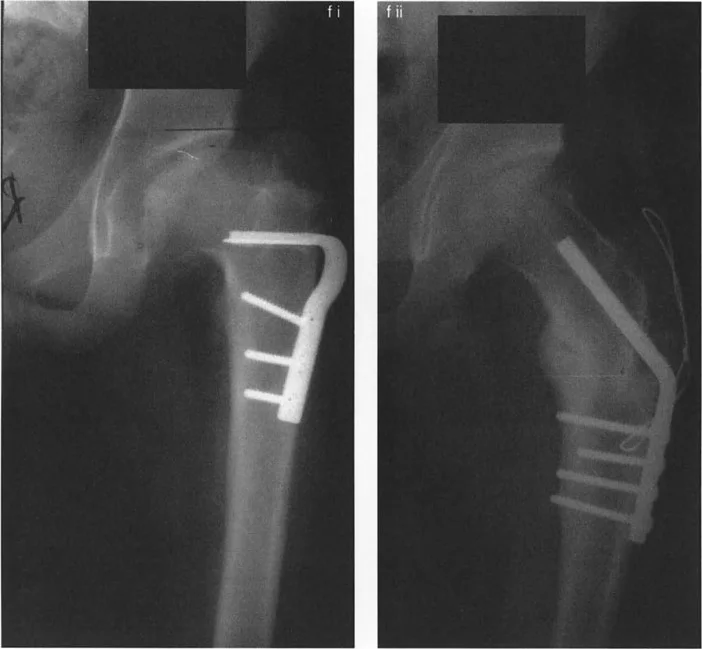

صور توضح حالة كسع الورك مع تضخم المدور الكبير قبل وبعد إجراء قطع عظم واغنر، حيث يتم تصحيح المحاذاة ونقل المدور الكبير.

صور توضح حالة كسع الورك مع تضخم المدور الكبير بسبب مرض بيرثيز، وعلاجها باستخدام قطع عظم مورشر مع التثبيت الداخلي.